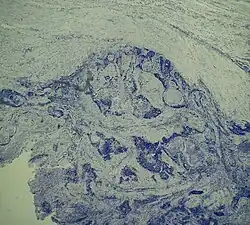

Строение карциномы в значительной степени зависит от структурно-функциональных особенностей клеток органов, из которых она развилась. Так, из клеток, контактирующих с внешней средой (эпителий кожи, слизистой оболочки рта, пищевода, гортани, прямой кишки), развивается опухоль, состоящая из многослойного плоского эпителия (ороговевающего и неороговевающего), которая носит название плоскоклеточной карциномы (плоскоклеточный рак).

Из эпителия железистых тканей (железы бронхов, молочная железа, простата) развивается опухоль железистой структуры (железистый рак) — аденокарцинома.

Для высокодифференцированных опухолей характерно строение, близкое строению ткани, из которой образовалась данная опухоль. В случае средне- и малодифференцированных опухолей сходство структуры опухоли и исходной ткани снижается, становится стёртым. Иногда клеточный и тканевой атипизм новообразования могут быть настолько выраженными, что определить тканевую принадлежность опухоли практически невозможно (недифференцированные опухоли). Как правило, они характеризуются высокой степенью злокачественности (то есть способностью образовывать метастазы).

В зависимости от преобладания в структуре опухоли стромы (соединительной ткани) или паренхимы (раковых клеток), различают простой рак, в котором строма и паренхима развиты в одинаковой степени, медуллярный рак, в структуре которого преобладает паренхима, и фиброзный рак (скирр), в котором преобладает строма.